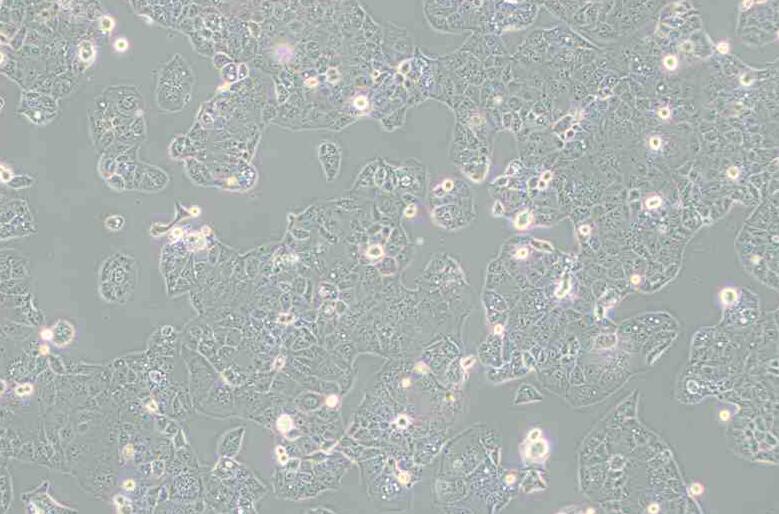

HEC-1-A(人子宫内膜腺癌细胞)

HEC-1-A

上皮细胞样

细胞背景描述 HEC-1-A细胞及其亚株HEC-1-B细胞是H·Kuramoto及其同事于1968年从一位ⅠA期子宫内膜癌患者身上分离得到的。PAF可以诱导,HEC-1-A细胞c-fos的表达。

细胞形态 上皮细胞样

细胞类型 肿瘤细胞

生长特性 贴壁细胞